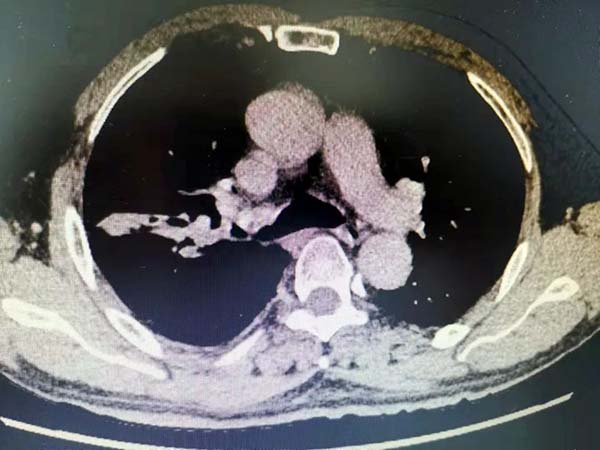

患者杨某,男,66岁,因“刺激性咳嗽”初步诊断为肺部肿瘤,为求进一步治疗来我院就诊。经CT、纤支镜及病理检查发现,病灶位于肺部右上叶支气管口处。肿瘤侵犯肺门严重、肿大淋巴结与血管紧紧挨着,同时患者出现营养不良的迹象,无法进行常规切除手术。科室主任曹忠宇为患者制定了“先新辅助、再进行右肺上叶袖式切除”的手术方案,在确保患者肿瘤彻底切除的前提下,最大限度地减少手术对患者的创伤,保留其肺部。前期先为患者进行化疗免疫双联新辅助技术(紫杉醇卡铂联合PD_1方案),经过两次新辅助治疗后,检查结果显示,肿瘤明显有缩小迹象。科室随即安排为患者进行全胸腔镜下右上肺叶袖式切除手术。